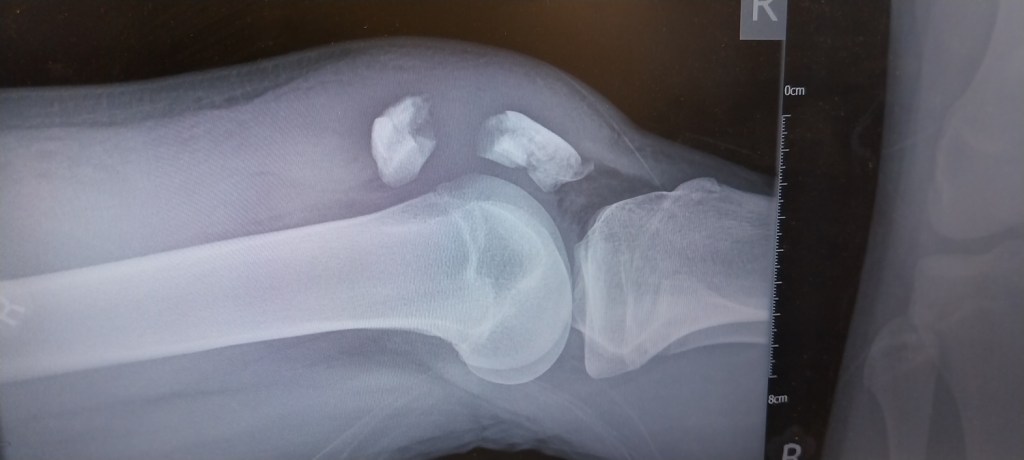

So this is the x-ray from the hospital that evening, those two pieces at the top are his patella and should be one. In fact there were around 6 pieces in total and he’d made a bit of a mess of his knee for sure. It happened rugby tackling his friend, not in PE, no. Instead at lunch, playing around. His knee was very painful and like a balloon. The ambulance said 3 hours to get there, so I turned up, drove across the school grass, loaded him in the front seat in agony and off to A&E. Roadworks at the front of the hospital, meant the drop off spots weren’t available. So we parked as normal in the car park, how we got him down the stairs and across the road I’ll never know, then an angel of a woman ran off and came back with a wheelchair for us and we wheeled him in. I remember well when they brought up his x-ray and nurses came from across the room to look at it, saying he’s done a “proper job of that”! Yes, yes he has.